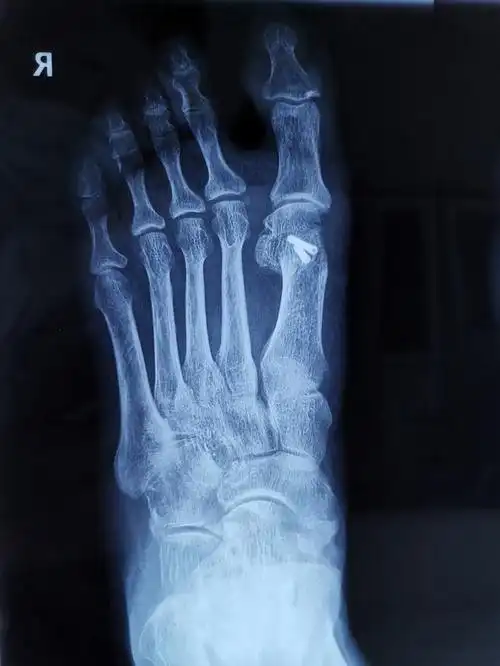

广济手足外科医院近期病例分享之:拇外翻

微创手术治疗拇外翻,医保报销,费用低,术后即可下地

足底行走痛 原来是"大脚骨"惹的祸

陈圣英分析拇外翻矫正削骨不是关键矫正才是关键